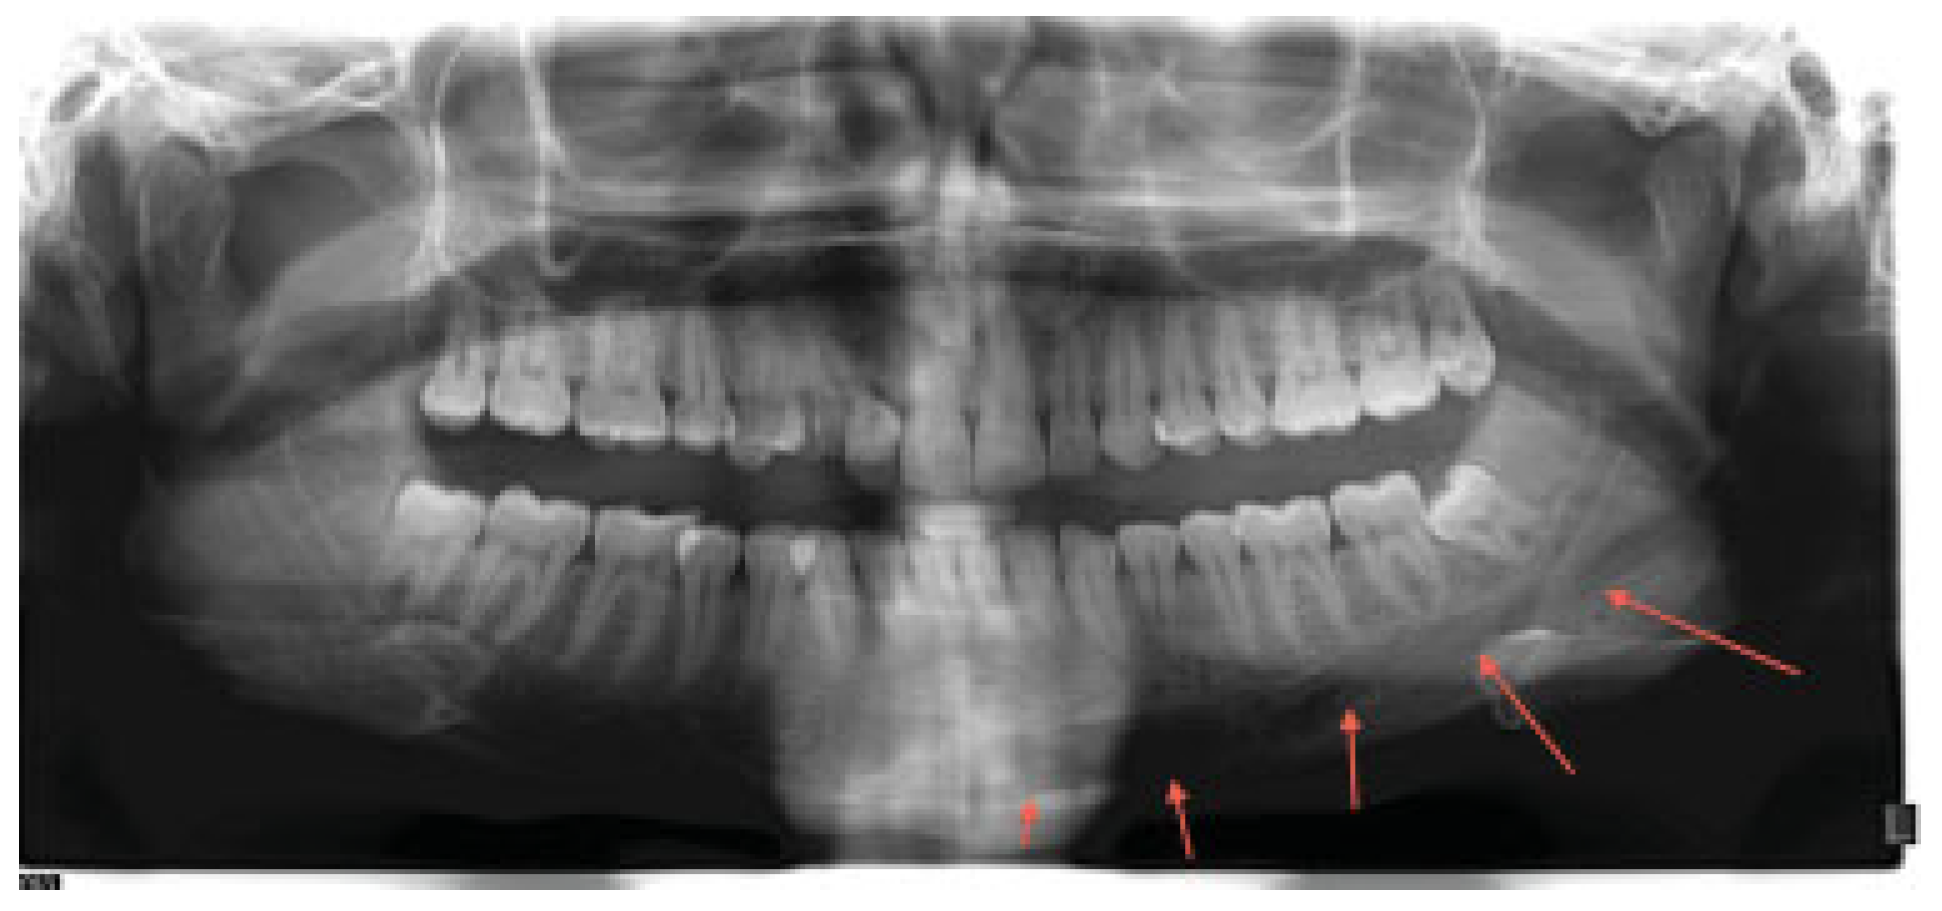

Grummon cephalometric analysis and analysis on the OPG showed a deficiency of 9 mm in the anterior region and 5 mm in the posterior region. Patient was planned for surgical management sequenced in two stages with addressing the hard tissue corrections in the first stage and soft tissue corrections in the second stage.

Figure 5. Postconsolidation and distractor removal, orthopantomographic view.